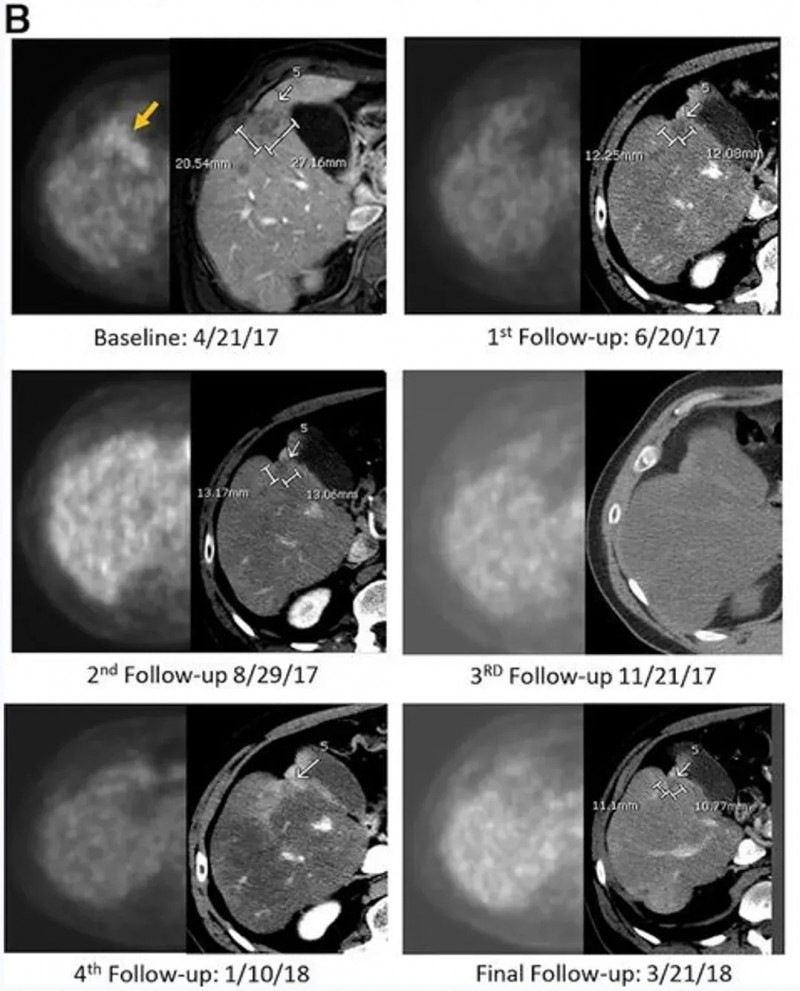

下图展示了一例59岁男性Kras突变型直肠癌患者的影像对比图:该患者既往接受过3线治疗,在接受IM96 CAR-T治疗后,其肺部、肝部的转移病灶均显著缩小。

▲图源“JCO”,版权归原作者所有,如无意中侵犯了知识产权,请联系我们删除

治疗结果显著:CAR-T输注6周后,正电子发射断层扫描(PET-CT)显示肝脏内原氟脱氧葡萄糖(FDG)阳性病灶完全无代谢活性,该完全代谢反应持续13个月;静脉增强CT提示目标病灶稳定或略缩小,无新增转移灶。治疗3.7个月时,PET扫描显示肝脏仍维持无代谢活性,但胰头原发灶代谢活性升高,患者随即接受以5-氟尿嘧啶为放射增敏剂的胰腺肿块放疗,后续扫描显示原发肿瘤灶亦达到完全代谢缓解。

从生存期来看,该患者总生存期(OS)长达23.2个月——而多数IV期胰腺腺癌患者中位生存期仅5个月,意味着CEA CAR-T疗法让这位化疗耐药患者的生存期延长了近5倍(4.64倍)。

肿瘤标志物层面,以治疗中最低点计算,患者CEA下降81%、糖类抗原19-9(CA19-9)下降68%,且两类标志物均在治疗后2-3个月内恢复正常。病理分析进一步显示,肝肿瘤活检标本出现大面积透明纤维化,无正常肝组织损伤迹象,且标本中检测到大量CAR+细胞。